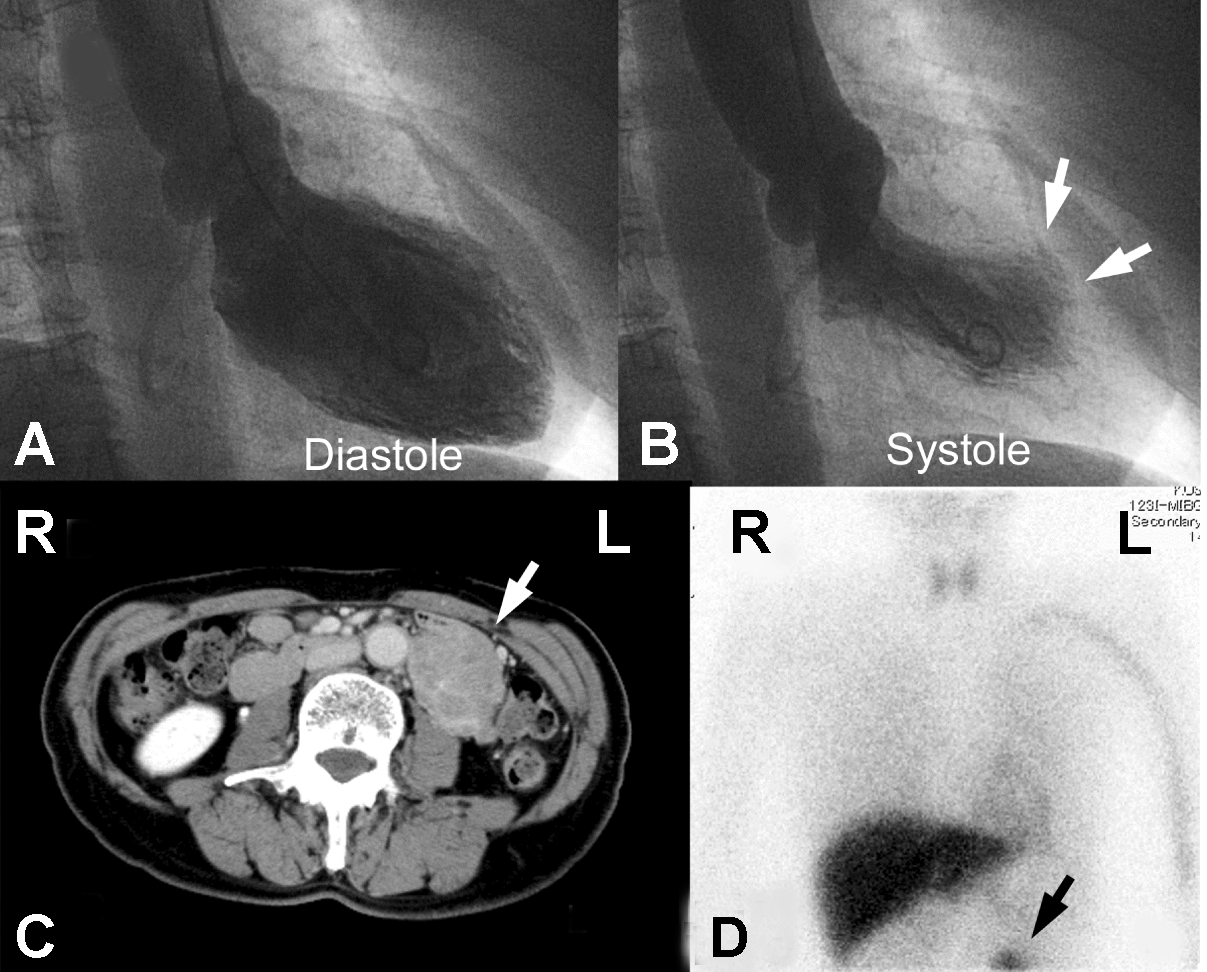

A 61-year-old female who was visiting a doctor for consultation for the presence of a breast mass, suddenly developed headache and chest pain and therefore was transferred to a hospital. Although her electrocardiogram revealed no significant ST-T change, the troponin I level was 3.57 ng/mL. Coronary angiography was normal and left ventriculography demonstrated anterior hypokinesis at the mid-ventricular level. (Figure 1A-B) Transient inversions of T waves in the anterolateral leads and normalization of the abnormal wall motion in the following days led to a diagnosis of Takotsubo cardiomyopathy. Iodine-123 labelled metaiodobenzylguanidine cardiac scintigraphy demonstrated anterolateral defects in the delayed phase and the heart to mediastinum ratio increased to 2.5. Computed tomography (CT) scan demonstrated a paraaortic mass in her left abdomen. (Figure 1C) She underwent simultaneous operations for the breast cancer and the paraaortic mass. When a surgeon manipulated the mass during the operation. Her blood pressure rapidly increased to over 200 mmHg, with ventricular tachycardia. Diagnostic studies performed after stopping the operation showed pulmonary congestion and anterior hypokinesis with T wave inversions in the leads I, II, III, aVL, aVF and V2-6. The retrospective findings of metaiodobenzylguanidine scintigraphy showed an abnormal uptake in the paraaortic mass. (Figure 1D) Further examinations of the mass resulted in a diagnosis of ectopic pheochromocytoma, also known as a paraganglioma, which was successfully resected. The histological findings of the mass demostrated that almost all the tumor cells were round with an eosinophilic, granular cytoplasm and that they were arranged in compact cell nests called Zellballen. Immunohistochemical staining showed positive results for chromogranin A and negative results for calretinin and Ki-67. Genetic testing was not performed because of patient's negative falimily history. She was discharged without any perioperative complications and was administered postoperative chemotherapy for breast cancer. One year after the operation, CT scan did not demonstrate any evidance of recurrence of the pheochromocytoma or the breast cancer. |